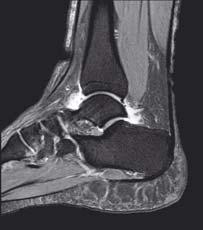

zwyrodnieniowa stawu skokowo-goleniowego

Zmiany w stawach stopy w przebiegu reumatoidalnego zapalenia

Staw skokowy dolny